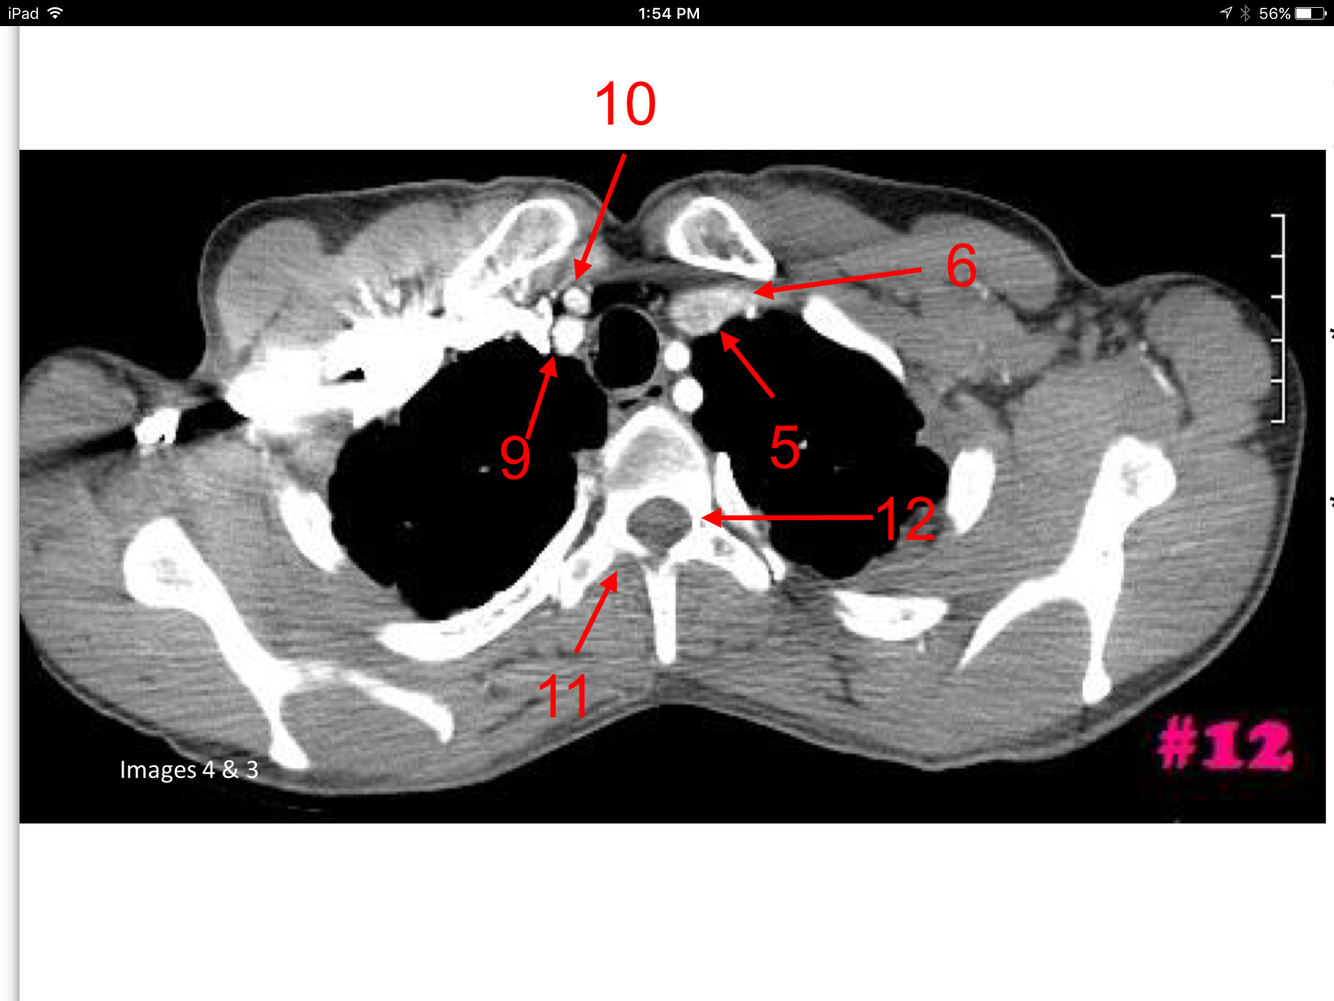

10

Q

A

Rt and Lt common carotid arteries

Rt and Lt internal jugular veins

Isthmus of the thyroid gland

Rt and Lt lobes of the thyroid gland

Rt and Lt vertebral arteries